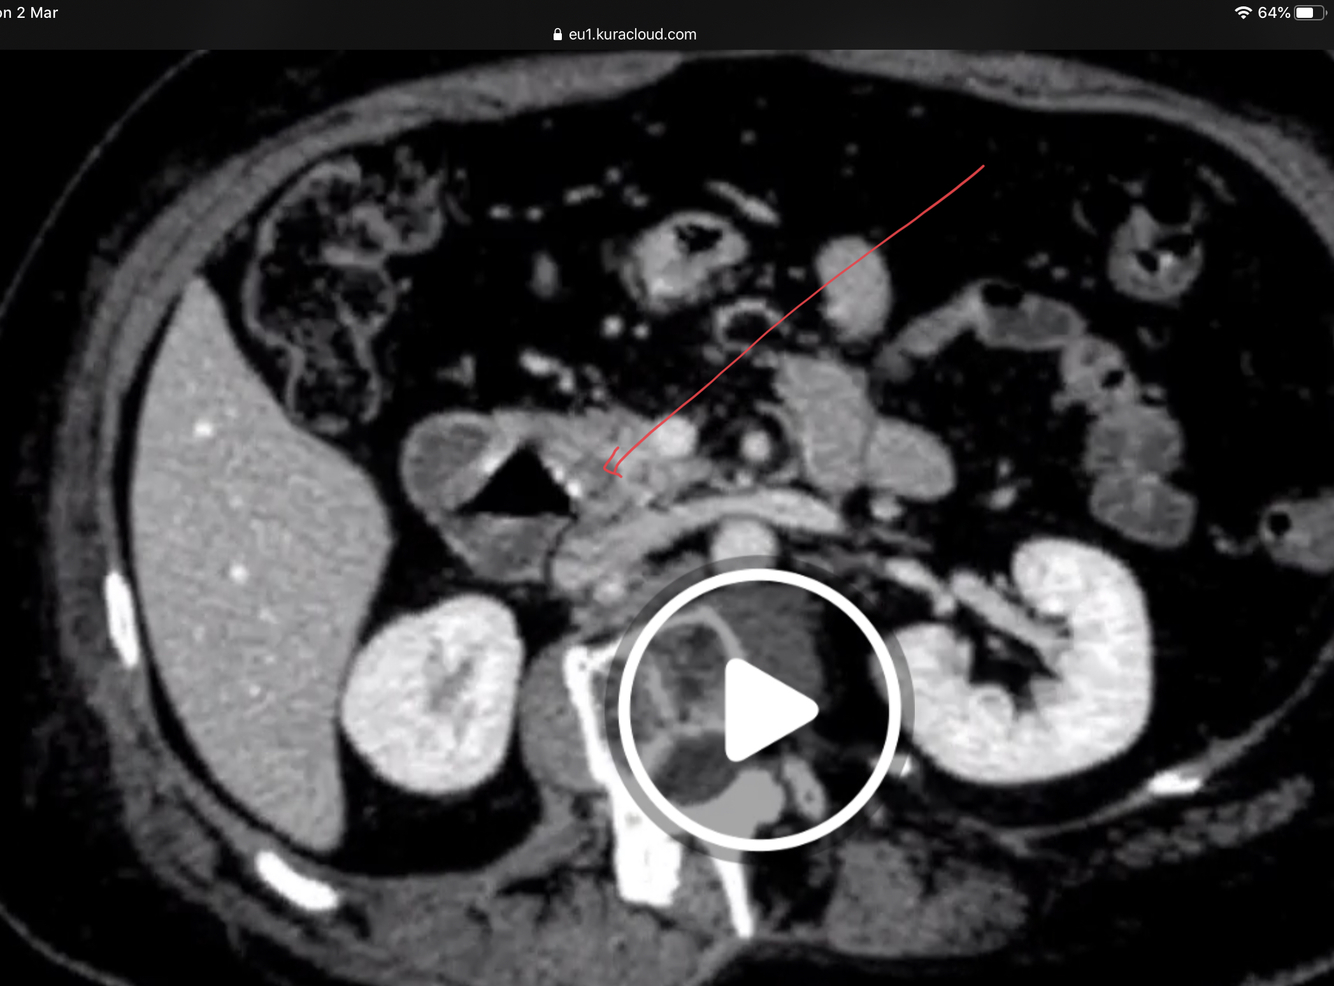

What would you expect to see in a CT scan for a CBD gallstones